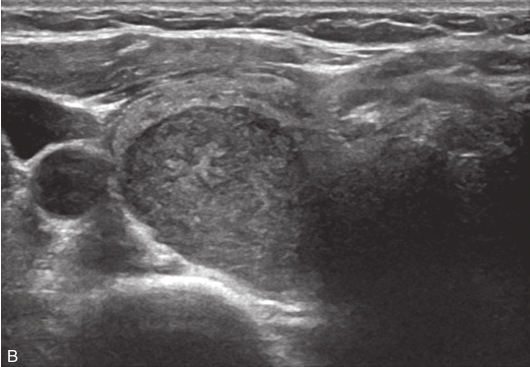

甲状腺左叶上极及下极分别可见一个低回声,大小约为0.8cm×0.9cm×0.6cm,边缘模糊,纵横比>1,内可见多发点状强回声;CDFI示结节内均未见明显血流信号。双侧颈部可见多发肿大淋巴结,其中左侧Ⅲ区可见一个大小为2.2cm×0.8cm、形态规则、淋巴门回声偏心、皮质回声增厚的结节;CDFI示淋巴结内可见丰富血流信号,见图1-9-3。

图1-9-3 甲状腺髓样癌及颈部淋巴结常规超声图像

A.甲状腺左叶上极低回声结节灰阶超声图像;B.CDFI示未见明显血流信号;C.左侧Ⅲ区结节灰阶超声图像;D.CDFI示结节内可见丰富血流信号